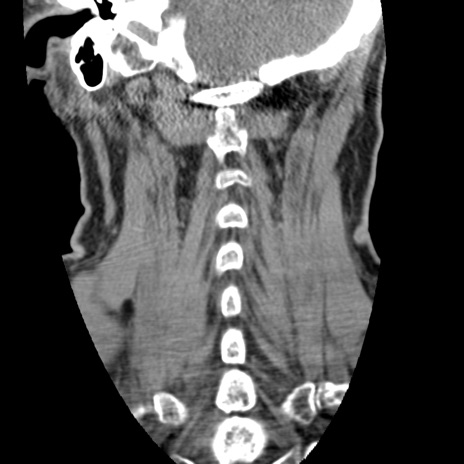

症例50 頚椎CT(冠状断像)

【症例】60歳代女性

【主訴】後頭部〜右後頸部にかけての痛み

【現病歴】本日飲食店でコーヒーを飲んでいたところ、突然後頭部〜右後頸部にかけて痛みが出現し、右上肢の感覚障害を伴ったため救急要請。

【身体所見】脳神経学的に明らかな異常所見を認めず。右上肢に軽度の感覚障害あり。

異常所見と診断は?